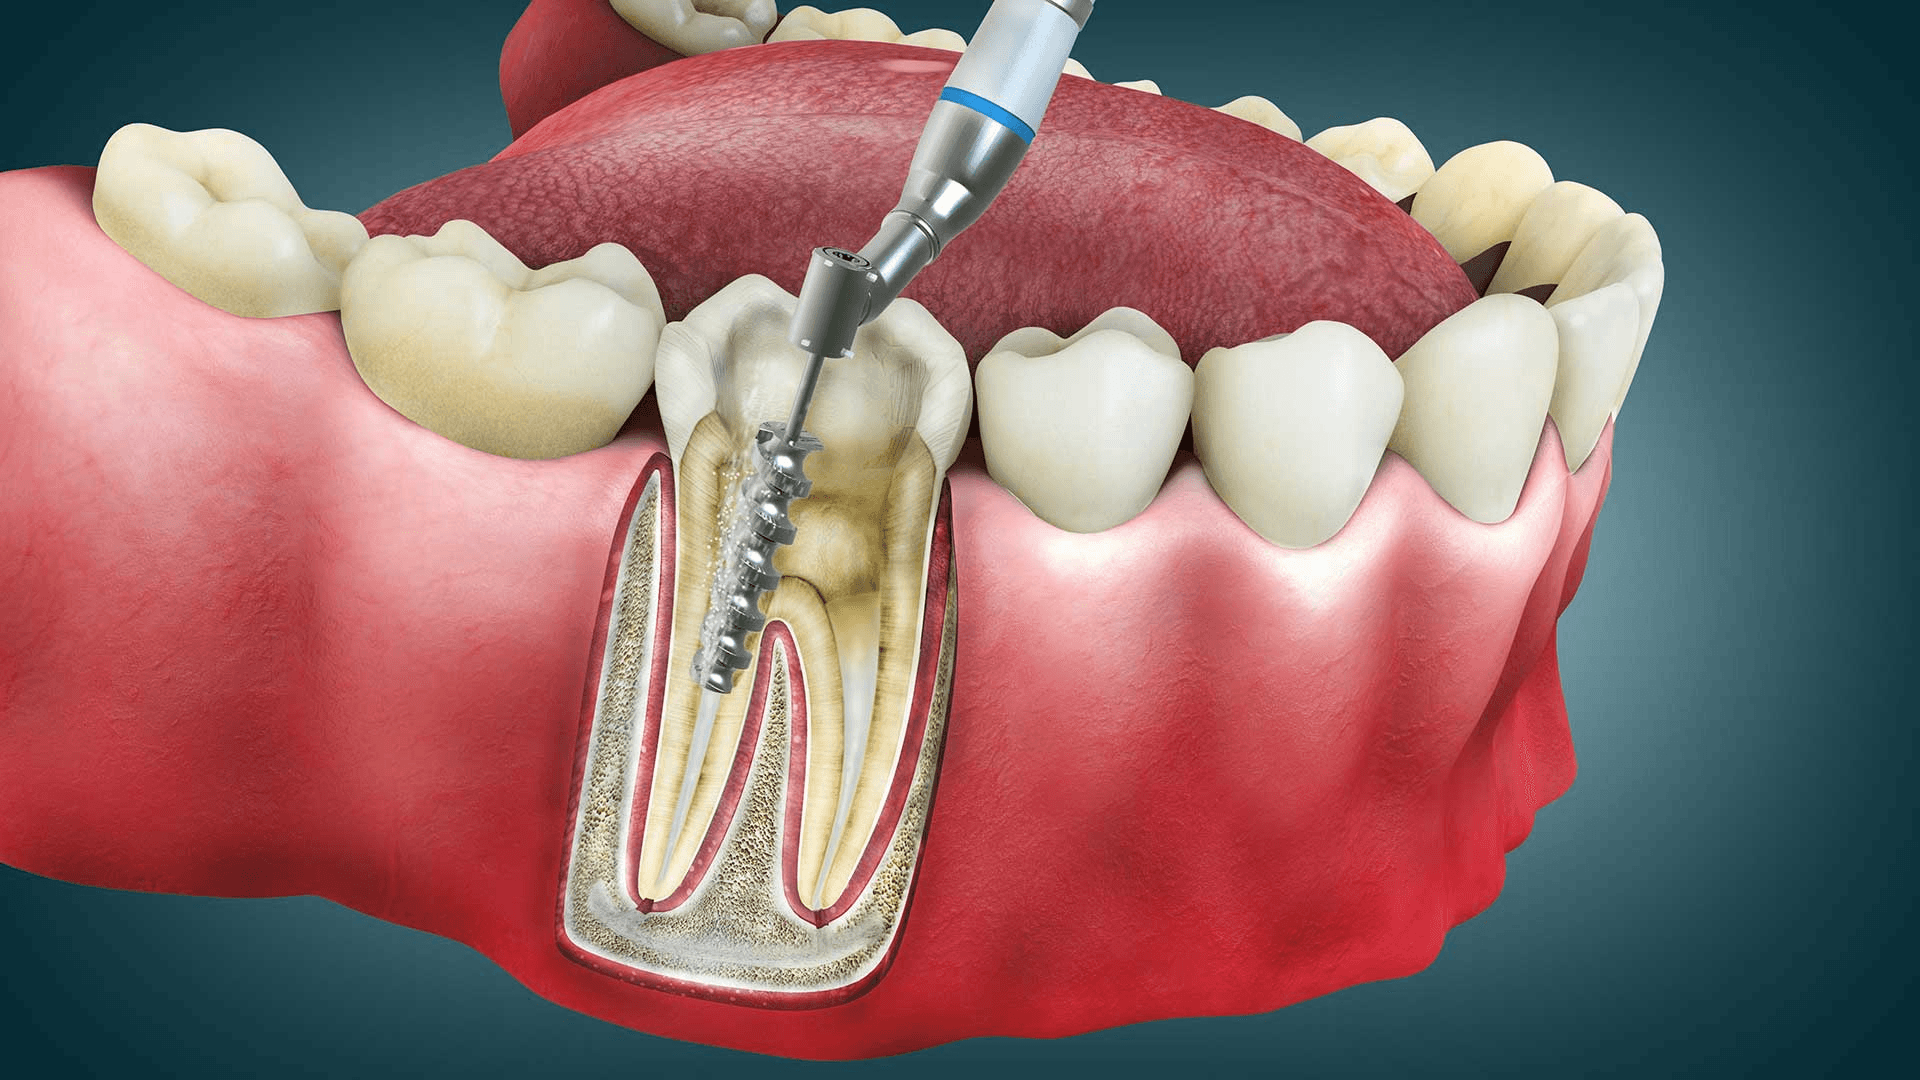

Root Canal Therapy

If decay reaches the inner pulp of the tooth, a root canal may be necessary to remove the infected tissue and prevent further complications. After cleaning and sealing the tooth, we typically place a crown for added durability.